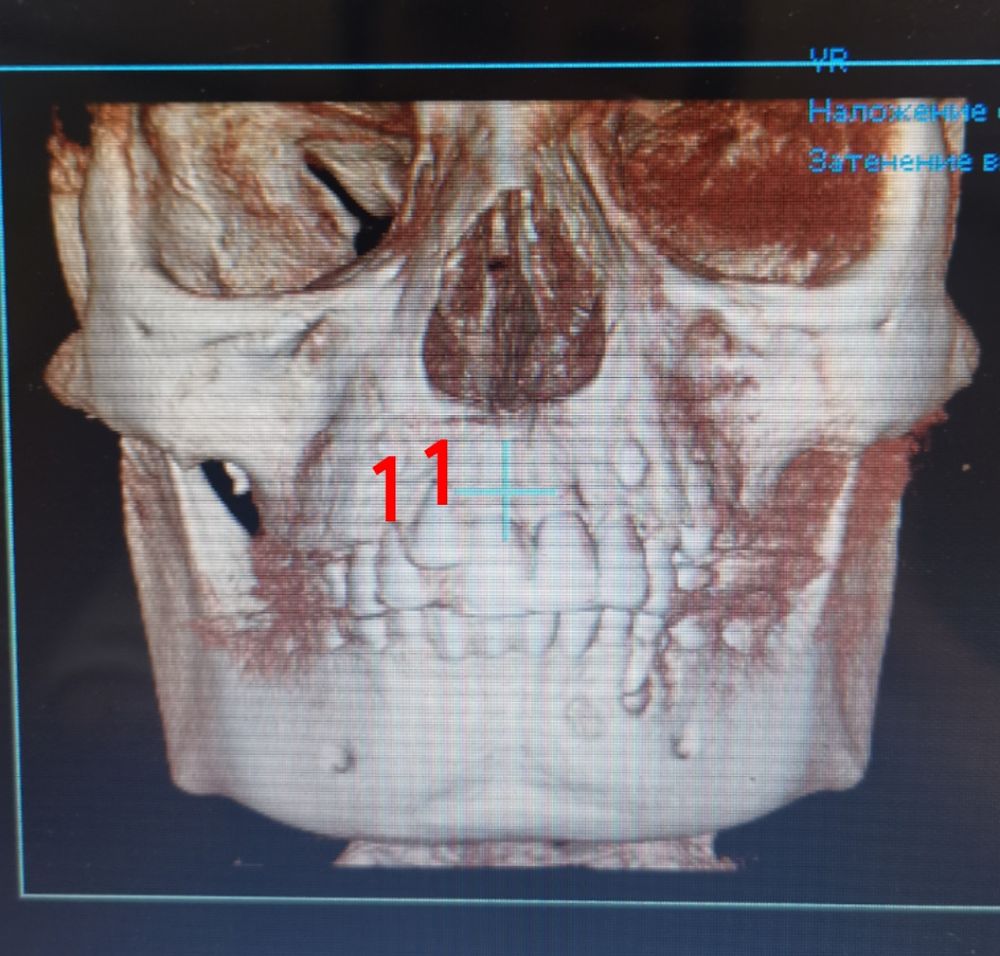

а это точно ваш снимок? или просто сделан давно? на снимке передние верхние зубы молочные, а на вашем фото верхние уже коренные стоят

Таша, снимок сделан 2 недели назад как и фото. Пару дней назад вот прислали на почту.

Вот они два одинаковых. И на том снимке пломбы как раз на тех, которые лечили

Но у нас в меня он видимо, у меня было клыков по три штуки. То есть сначала одни молочные, выпали рано. Полезли ещё, думали коренные а оказались молочные. Выдрали их, так лезли ещё уже коренные. С сыном делали 3д снимок. Эти два зуба полностью одинаковые, но один лишний. И если его не удалить, то новому который брат близнец некуда будет встать(

Анна, там реально лишний резец. И он вырос далеко от центрального резца, потому что ему мешал резец, который ещё в десне. В целом, у ребёнка узкая верхняя челюсть, у детей должны быть диастема и тремы (щели между резцами), это запас места для роста новых зубов. Скорее всего, сейчас лишний зуб выдернут, дождутся, когда вылезут все резцы и поставят расширяющую пластинку на верхнюю челюсть.